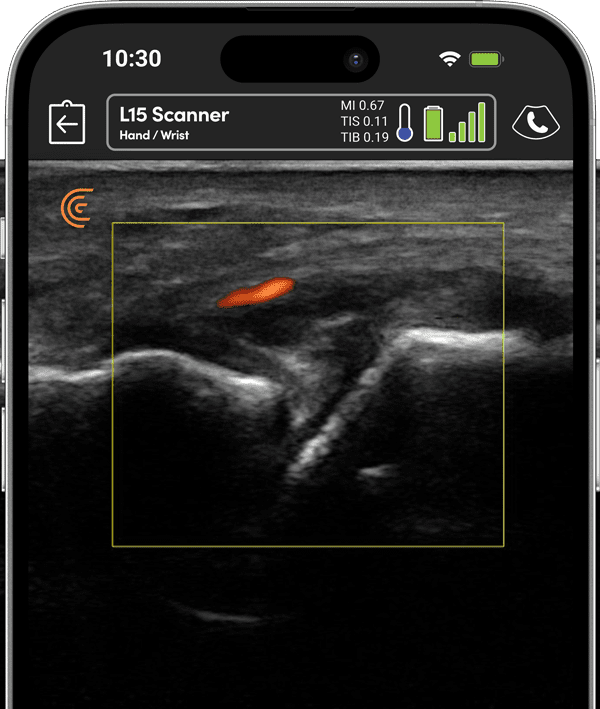

Get detailed joint, soft tissue and blood vessel imaging in real-time for dynamic assessments of inflammatory arthritis, lupus, vasculitis and more. Affordable and easy to use for novice and expert users.

A growing body of clinical and research studies have demonstrated the utility of ultrasound for providing better diagnostic and treatment decisions in patients with rheumatic diseases.” With high-definition imaging, sensitive power doppler and AI-powered features such as voice controls for a small fraction of the cost of cart-based systems, Clarius HD3 is a popular choice for rheumatologists performing in-clinic ultrasound exams.

With 8 times the processing power of most handheld ultrasound systems, Clarius HD3 gives you sharp and clear images of inflammation, joint effusions, synovitis, bone erosions, and tendon and enthesis involvement for optimal diagnosis and monitoring patient progress over time.

Optimized for Rheumatology, visualize blood flow to assess inflammation and guide precise interventions.

In this video Dr. Bardi uses B-mode and power Doppler to examine the MCP, DIP and PIP joints. High-resolution ultrasound can provide valuable real-time imaging of the synovial membrane, tendons, cartilage, and cortical bones, contributing to accurate diagnosis and treatment planning.